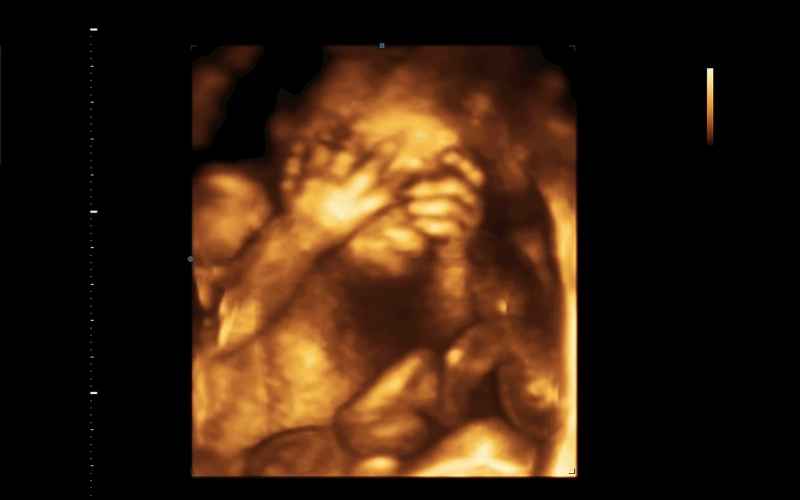

Thai nhi được 22 tuần tuổi: Cân nặng khoảng 430gram và dài chừng 27.8cm. Khi siêu âm chúng ta sẽ thấy rõ các đường nét thể hiện trên khuôn mặt của bé. Bên cạnh đó, các tuyến tụy cũng đã được hình thành, làn da của bé được bao phủ bởi một lớp lông tơ mềm mịn.

Thai nhi tháng thứ 6 đang ở tuần 21- 24 của thai kỳ. Lúc này, em bé đã có sự thay đổi vượt bậc về kích thước, trọng lượng và các cơ quan, bộ phận trên cơ thể. Cụ thể:

Thai nhi được 21 tuần tuổi: Cân nặng khoảng 360 gram và dài 26,7 cm. Lông mày và mí mắt của bé đã xuất hiện, bé cũng có thể nghe được âm thanh từ bên ngoài.

Thai nhi được 23 tuần tuổi: Cân nặng khoảng 500 gram, dài khoảng 29cm. Thai nhi 34 tuần tuổi đã có những chuyển động, cựa quậy, đạp trong bụng mẹ mà chúng ta có thể cảm nhận được rất rõ ràng. Hệ hô hấp của bé cũng đang dần hoàn thiện để chuẩn bị bước sang giai đoạn cuối cùng trước khi chào đời.

Thai nhi được 24 tuần tuổi: Cân nặng khoảng 600gram và dài khoảng 30 cm. Trong tuần cuối tháng thứ 6 của thai kỳ, não bộ và phổi của thai nhi đang trong quá trình hoàn thiện nốt.